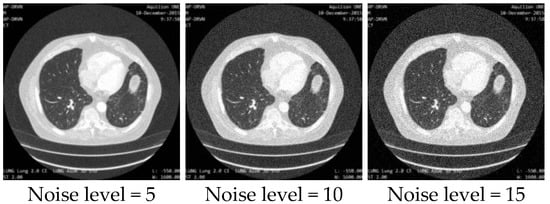

Figure 10. Sampled image patches with different noise levels as the dataset for the image noise estimation network. - Dataset for the image quality enhancement network: All 1600 lung CT images were corrupted with random Gaussian white noise (5, 10, 15) and down-sampled to 256 × 256 images. Then, 1400 pairs of degraded and target images were used as the training set, while the other 200 pairs of images were used as the testing set. Figure 11 shows some sampled degraded images with noise and low-resolution.

Figure 11. Sampled images with low resolution and different noise levels as the dataset for the image quality enhancement network.